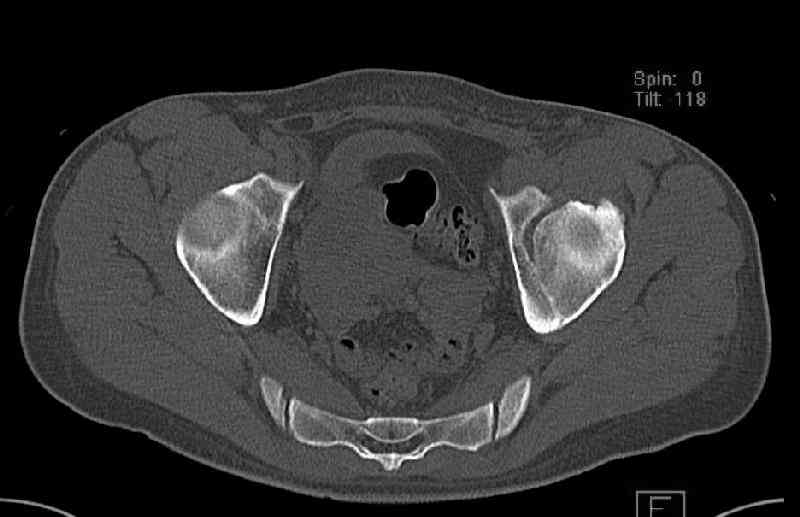

Мужчина 33 лет получил травму в шахте (придавило вагонеткой) 6 недель назад. Изолированное повреждение вертлужной впадины.

В местной больнице отлежал несколько недель на вытяжении. После выписки амбулатрный травматолог направил в институт. На сегодня, похоже, уже имеется неправиильное сращение. См. картинки.

Dear all,A male 23 y.o. injured 6 weeks ago - mine trauma, impacted by a carriage. Isolated injury of the acetabulum. At the initial hosptial was on bed traction some weeks. After discharge visited anotheк orthopaedic surgeon who referred him to our unit. To date looks like a malunion. Images attached. The question is about what to do now - either leave it as is or perform open reduction? If the latter what approach, reduction manoeuvres and fixation would you advice? Thx in advance!

My concern would be that the risk of leaving it malreduced is very high. It appears to be primarily a gap rather than a step in the articular surface. Do you have any CT views that show an articular step?

The last two images from the 3-D CT scan certainly makes the fracture look worse than the plan radiographs.

Some more images. Does it help to guess which part of the acetabulum is displaced?